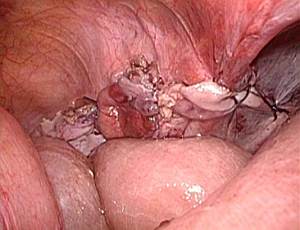

���`�ɂP�Omm�̌��������ē����������Ȃ��̒��ɑ}�����A���ǂɊJ�������i�w���j�A��j���m�F���A���b�V���V�[�g�����ɂ��Ăĕ����܂��B

�����ɂ͂Q�`�R�̂Tmm���x�̏����Ȍ��������Ď�p�{�s���܂����A�����͎�p��A���Ԃ��o�ĂقƂ�ǖڗ����Ȃ��Ȃ�܂��B

��p�̓����ɓ��@���Ă��������A�p��Q�`�T���őމ@�ƂȂ�܂��B